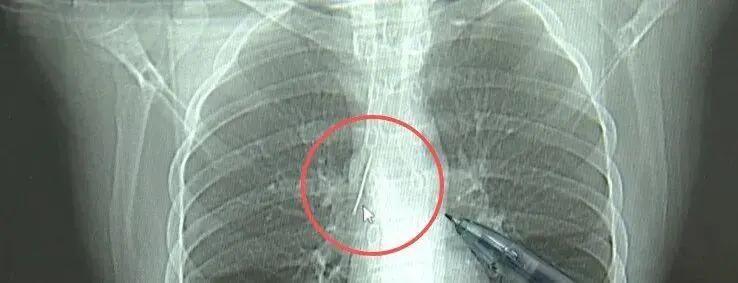

小陆参加征兵体检时,胸片检查显示胸腔内存在金属高密度影,形态与细针一致。后续CT检查进一步确认,这枚缝衣针斜插在肺组织内,针尖直指上腔静脉和胸主动脉等大血管,位置极度凶险,稍有不慎就可能引发血管损伤,危及生命。